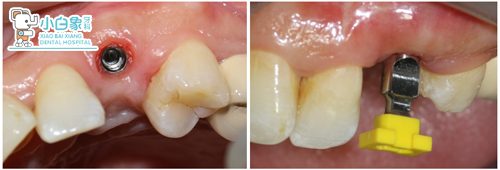

2017年11月24日

23取出愈合帽,装基台,试戴全瓷冠,粘结,调合抛光。

基台

戴牙